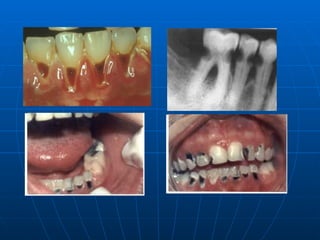

EARLY CHILDHOOD CARIES Early childhood caries would include, two variants: Nursing caries and rampant caries. The difference primarily exist in involvement of the teeth[ mandibular incisors ] in the carious process in rampant caries as opposed to nursing caries.

CLASSIFICATION OF EARLY CHILDHOOD CARIES All teeth including mandibular incisors Cause  multitude of factors TypeIII (SEVERE) Unaffected mandibular incisors Soon after first tooth erupts Cause  inappropriate feeding +lack of oral hygeine TypeII  (MODERATE) Involves molars and incisors Seen in 2-5 years Cause  cariogenic semisolid food +lack of oral hygeine TypeI (MILD )

SYNONYMS Nursing caries, Nursing bottle mouth, Nursing bottle syndrome, Bottle-Propping caries, comforter caries, Baby Bottle mouth, Nursing Mouth Decay, Baby bottle tooth decay, tooth cleaning neglect  NEW NAME Maternally derived streptococcus mutant disease (MDSMD)

RAMPANT CARIES Seen in all ages, including adoloscennce Affects primary and  permanent dentition Mandibular incisors are  also affected ETIOLOGY MULTIFACTORIAL Frequent snacks  Sticky refined CHO Decreased salivary  flow  Genetic background NURSING CARIES Seen in infant and  toddler Affects primary dentition Mandibular incisors are  not involved ETIOLOGY Improper bottle  feeding   Pacifier dipped in honey/other sweetner

RADIATION CARIES Radiography is frequently associated with  xerostomia  due to decreased salivary secretion,an increase in viscosity and low P H This and other causes of decreased salivary secretion may lead to a rampant form of caries, including the significance of saliva in preventing caries.

Three  types of defects due to irradiation Lesion usually encircling the neck of teeth amputation of crowns may occur  Begins as brown to black discolouration of tooth .occlusal surface and incisal edges wear away Spot depression which spreads from any surface